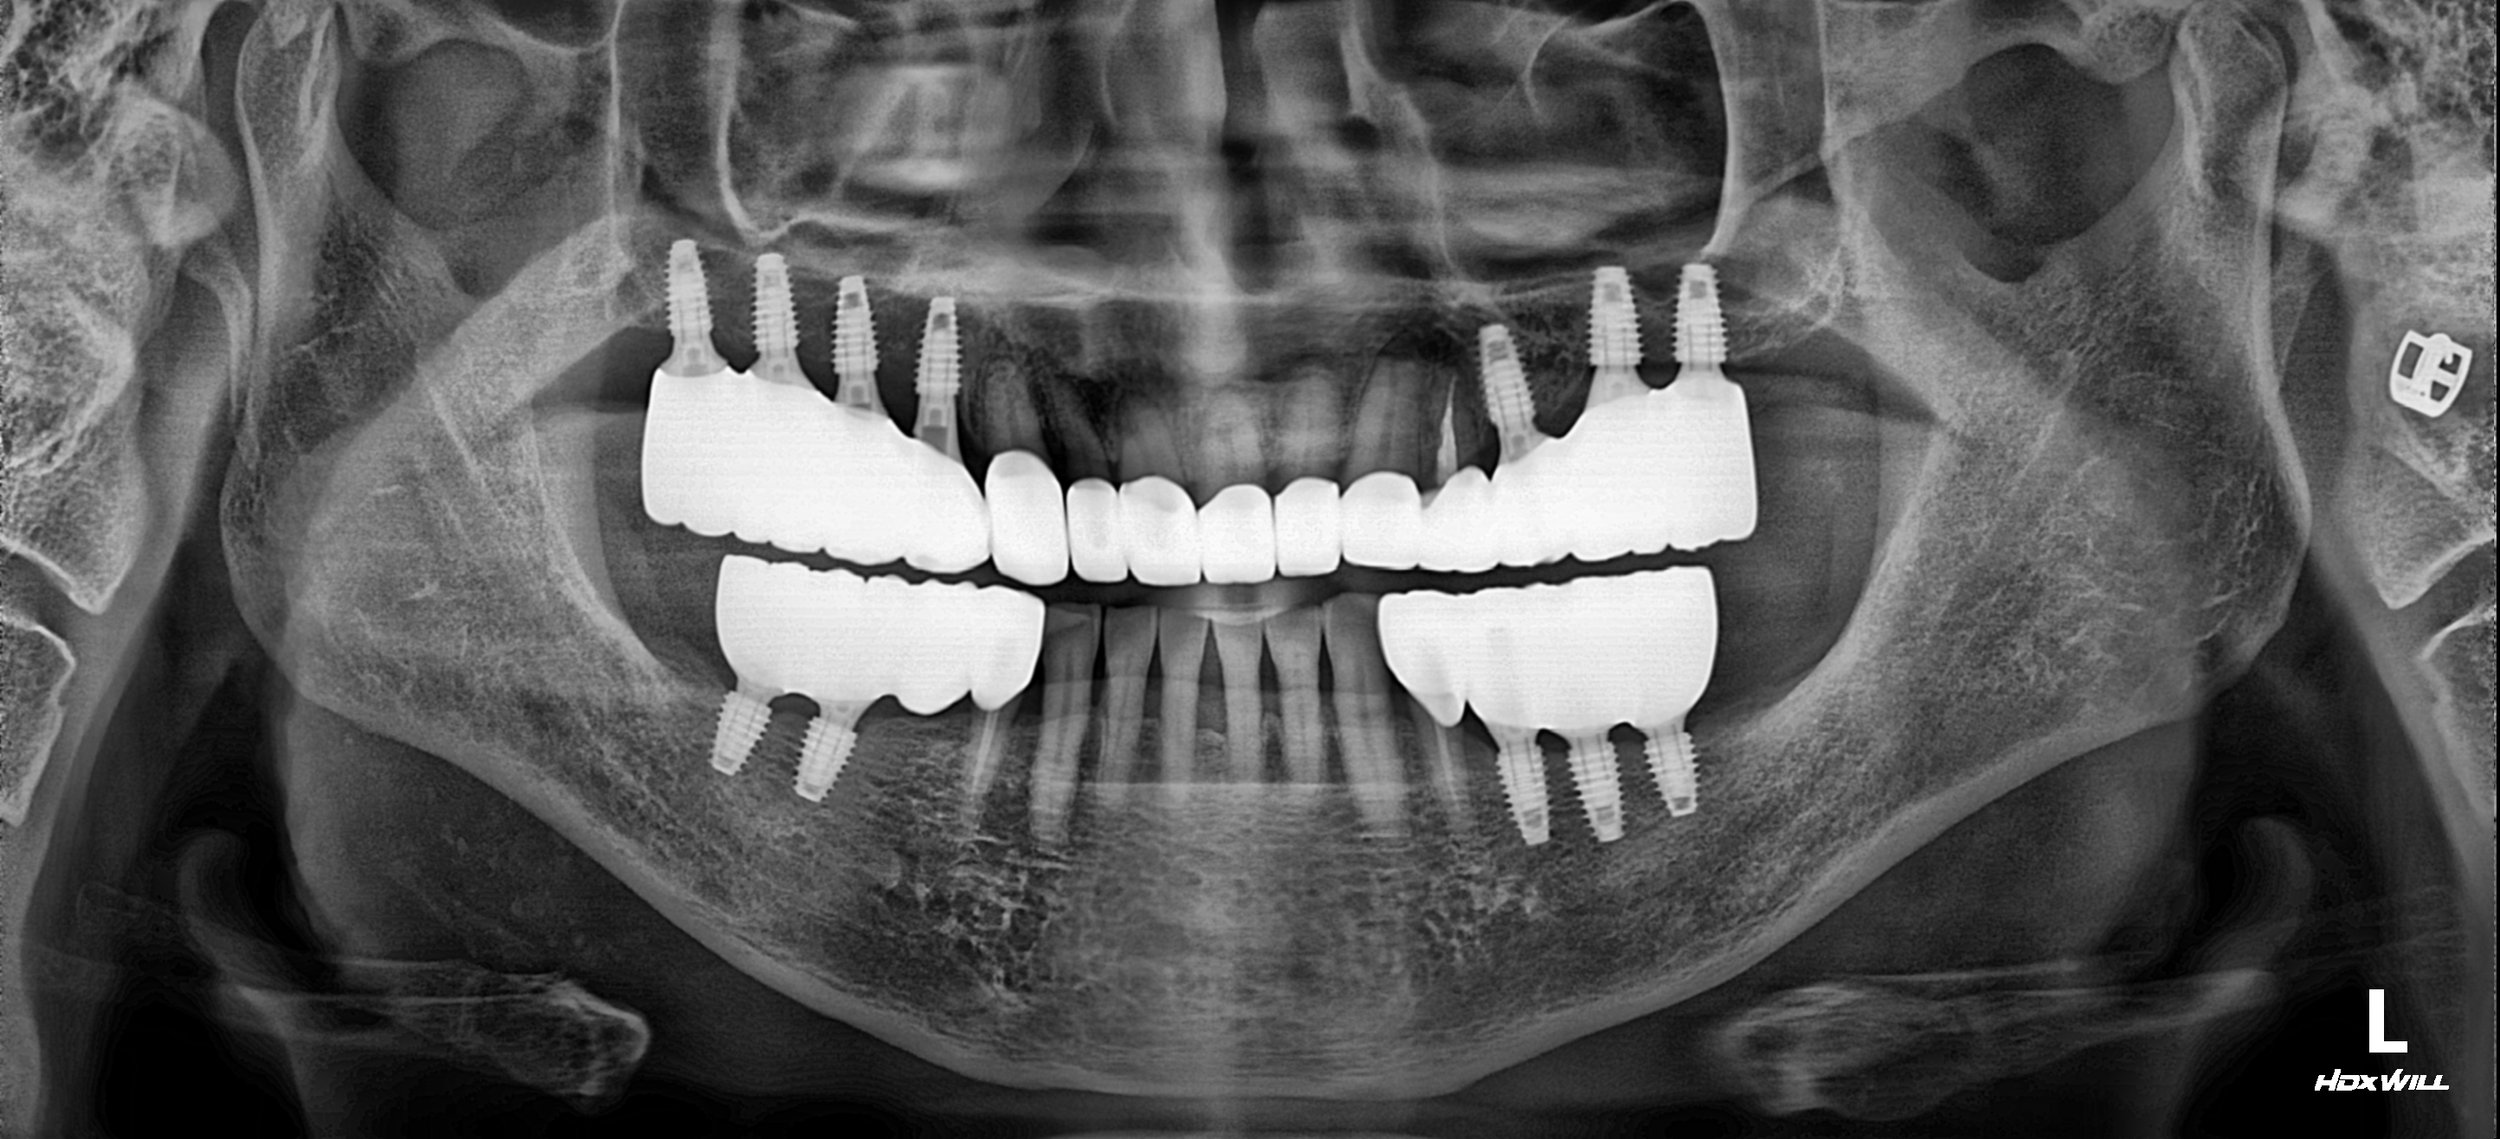

Treatment Objectives

• VDO Elevation: To create adequate vertical space for functional and aesthetic restorations.

• Bite Realignment: To transition the patient from a Class III underbite to a more neutral edge-to-edge relationship.

• Sinus Augmentation: To provide sufficient bone height for implant placement in the severely resorbed maxillary posterior regions.

• Functional Stabilization: To establish a repeatable bite position that prevents further mandibular deviation.

Treatment Approach

The rehabilitation required a careful balance between surgical foundation and prosthetic adaptation:

1. Surgical Phase: Bilateral maxillary sinus lifts were performed to facilitate the placement of implants in the posterior segments. This established the necessary foundation for the new occlusal scheme.

2. Occlusal Assessment: Following jaw relaxation (deprogramming) and clinical testing, it was determined that an edge-to-edge bite relationship was achievable. This position was selected to provide the most stable and reproducible centric relation.

3. Adaptation Phase: The patient was transitioned into temporary restorations at the newly elevated VDO. Over several months, the patient's neuromuscular system was monitored for adaptation to the edge-to-edge position. This phase was critical for ensuring comfort and long-term stability.

4. Final Delivery: Once stability was confirmed, the final implant-supported and tooth-supported prostheses were delivered. While not a "perfect" Class I occlusion, the height and positioning were meticulously set to prevent abnormal mandibular deviation, ensuring a sustainable and functional result.

The patient successfully transitioned from a state of total dental neglect and functional failure to a stable, fixed rehabilitation that has significantly improved his quality of life.